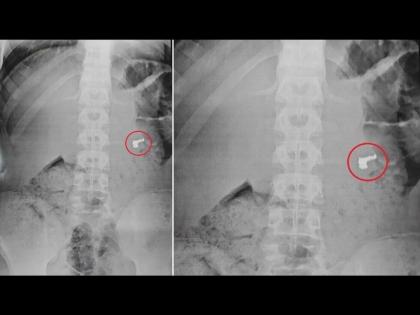

पण चोरांकडे काहीच सापडलं नाही आणि उलट चोर म्हणाले की, तुमच्याकडे काय पुरावा आहे की, आम्ही सोन्याची चेन चोरी केली. काही न मिळाल्यानंतर संशयितांना टेस्ट करण्यासाठी नेण्यात आलं. त्यांचा एक्स-रे केला तर सगळे हैराण झाले.

एका चोराच्या एक्स-रेमध्ये स्पष्ट दिसत होतं की, त्याच्या पोटात सोन्याची चेन आहे. त्यांना हॉस्पिटलमध्ये नेण्यात आलं आणि त्याच्यावर उपचार सुरू आहेत.